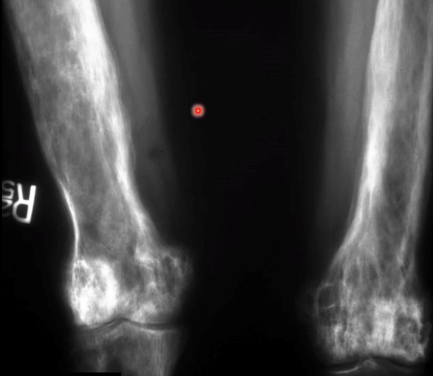

- Lyse des os longs en “brin d’herbe”

- Les lyses sont bien délimitées, avec une fin en “V”

vertèbres en cadre image Blade of Grass / Brin d’herbe / Candle Flame Signbanane enOstéodystrophie déformante osseux osteodytrophie